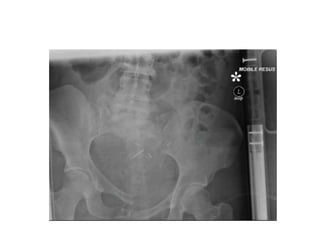

Normal pelvic radiograph

Pelvic fracture